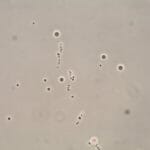

Sperm Counting